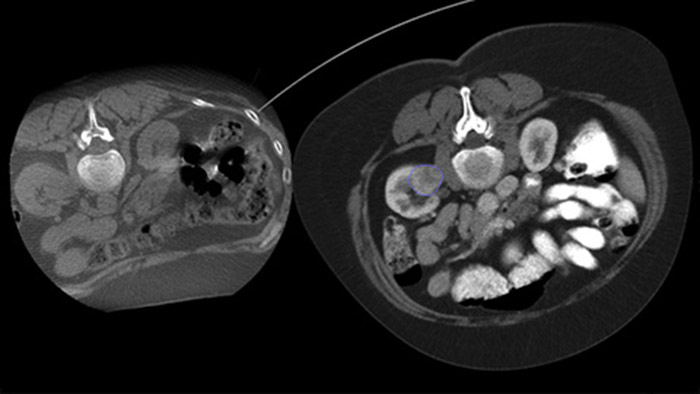

XperGuide Ablation* bietet umfassende Unterstützung bei der Behandlungsplanung und Echtzeit-Nadelnavigation. Die spezielle Parallaxenkorrektur ermöglicht die Planung von Nadelverläufen bei außermittigen Läsionen.1 Um eine möglichst gute Nadelposition für eine wirksame Ablation zu erreichen, zeigt dieses Tool den virtuellen Nadelverlauf an. Auch die Planung mehrerer Ablationsnadeln wird dadurch unterstützt. Außerdem werden Nadeleigenschaften wie Ablationszone/Isotherm angezeigt, damit die vollständige Tumorabdeckung vor der Ablation verifiziert werden kann.

Die perkutane Ablation (Hochfrequenz-, Mikrowellen- und Kryoablation) ist eine etablierte, minimal-invasive Behandlungsmethode für Nieren-, Leber-, Lungen- und Knochentumore. Dabei ist es besonders wichtig, den Tumor abzugrenzen und eine geeignete Anzahl an Nadeln und notwendigen Nadelverläufen festzulegen, damit der gesamte Tumor behandelt werden kann, ohne das umliegende Gewebe zu schädigen. Durch die präzise Navigation zur relevanten Läsion bei niedriger Strahlendosis und ohne Neupositionierung der Nadel werden die Erfolgschancen erhöht und das Komplikationsrisiko bei Biopsien und Ablationen reduziert. Der Endpunkt der Ablationsbehandlung kann mittels 3D-Bildgebung verifiziert werden, während sich der Patient noch auf dem Tisch befindet.

Mit Dual View kann ein 3D-Vorabbild (CT/MR/PET-CT) über ein intraprozedurales 3D-CBCT-Dual-Bild gelegt werden, um die Läsionen besser sichtbar zu machen und entscheidende Informationen für die Nadelplanung zu erhalten.

Mithilfe eines nach der Ablation erfassten CBCT-Bilds können Sie die Tumorabdeckung und damit die Vollständigkeit der Behandlung verifizieren.